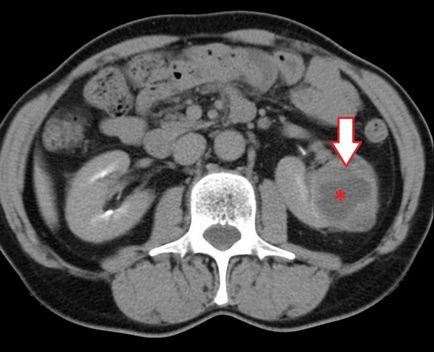

egy nagy tumor

Photo ciszták a vesében, a fent hivatkozott, azt mutatja, hogy a patológia végül nőnek a hatalmas mérete. Ebben az esetben, az hatással van a nagy területen test felületén okoz veseelégtelenséget és sok mellékhatással betegség.

Megjelenése tumorok

Figyelembe véve a ciszták a vese fenti képen látható egy nagy szürke folt. Ez a hely a kijelző egy nagy cisztás test, csatlakozik a test szöveteiben.